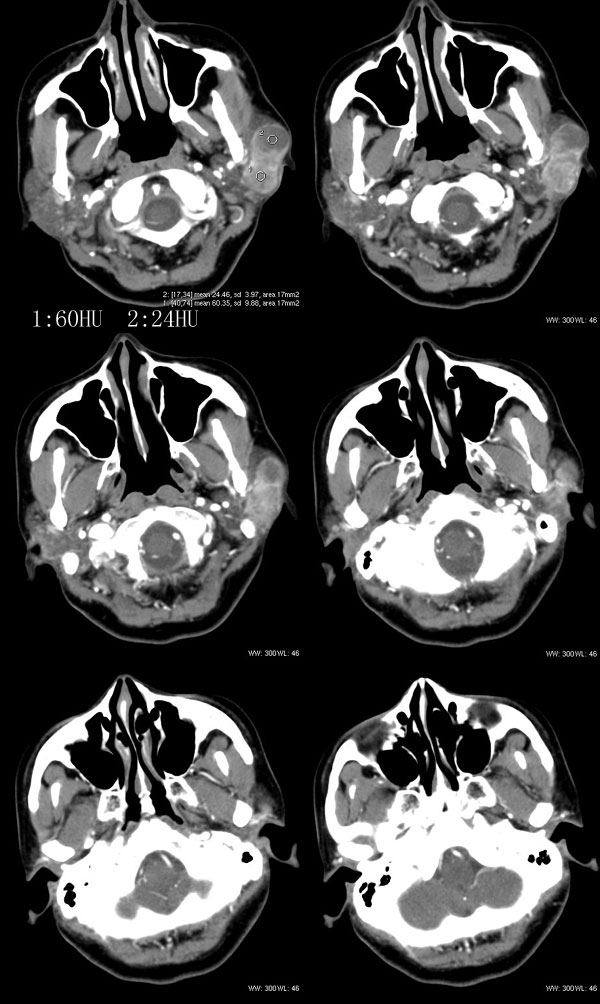

女性,43岁。左腮部肿物5年。体检:(肿物)质中,约5x4x4cm,边界清,固定。

左腮腺肿物,内可见低密度坏死区,增强扫描示肿块明显强化,且呈持续延迟强化,常规考虑腮混合瘤可能性大,但强化表现不太符合,不除外腮腺纤维血管瘤、神经鞘瘤、淋巴瘤及巨淋巴结增生症

考虑左侧腮腺混合瘤。  肿瘤较大,边清,囊变,强化明显,皮肤及淋巴结无异示